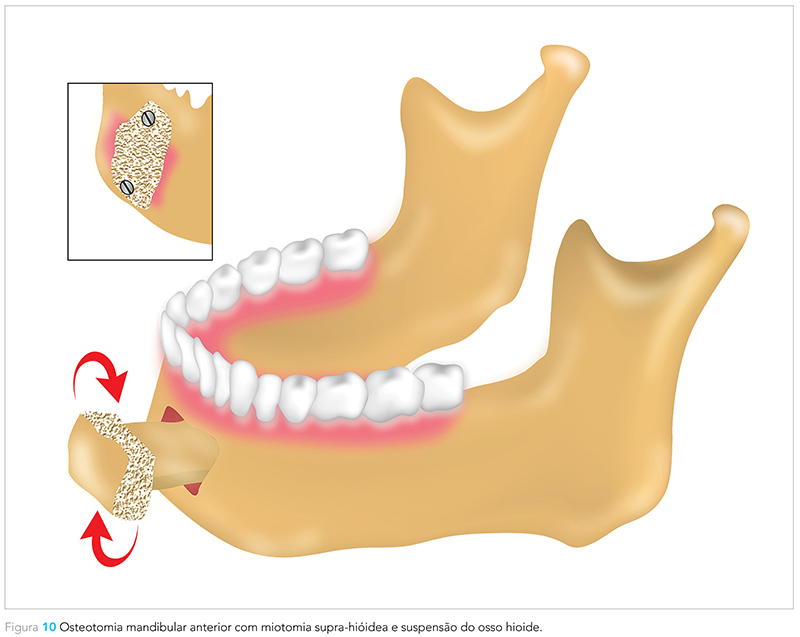

Outra técnica disponível é a osteotomia mandibular anterior com miotomia supra-hióidea e suspensão do osso hioide. A osteotomia envolve a região anterior da mandíbula, incluindo os tubérculos genianos, promovendo o avanço e a suspensão do hioide juntamente com a musculatura supra-hióidea. Da mesma forma que as técnicas anteriormente comentadas, essa também possibilita o aumento do espaço aéreo20,21 (Fig. 10).